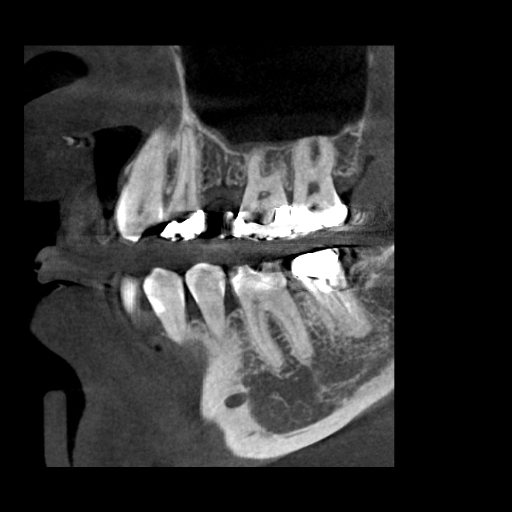

右上インプラント治療に伴うサイナスリフトの症例

Before

After

治療内容

右上の5番を抜歯され、インプラント治療を希望された患者様です。

副鼻腔があり、インプラントを埋入するための骨の量が足りないため、副鼻腔に骨を作る処置(サイナスリフト)を行い、同時にインプラント埋入しました。

理想的な位置にインプラントを埋入することができ、長期予後を獲得することができます。

担当歯科医師:平沼 佳朗

治療期間・回数

約10か月

費用

サイナスリフト込み¥671,000

リスク・副作用

術後に痛みや腫れ、出血を伴います。

口腔内の清掃不良によりインプラントの歯周病(インプラント周囲炎)になる可能性があります。定期的なメインテナンスが必要です。